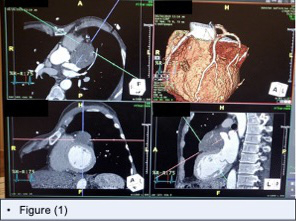

A 68-year-old male with a history of OSA was referred to cardiology by his primary care provider after an incidental finding of left ventricular hypertrophy on EKG. Examination was significant for a grade III late systolic murmur. Echocardiography revealed severe mitral regurgitation, mitral valve (MV) prolapse and an epicardial mass suggestive of a tumor. Cardiac CT demonstrated an epicardial tumor of the left atrial appendage, uplifting the left main coronary artery, displacing the proximal LAD and first diagonal branch (Diag)(figure 1). Cardiac catheterization ruled out significant CAD, but identified tumor blush from the Diag(Figure 2a).